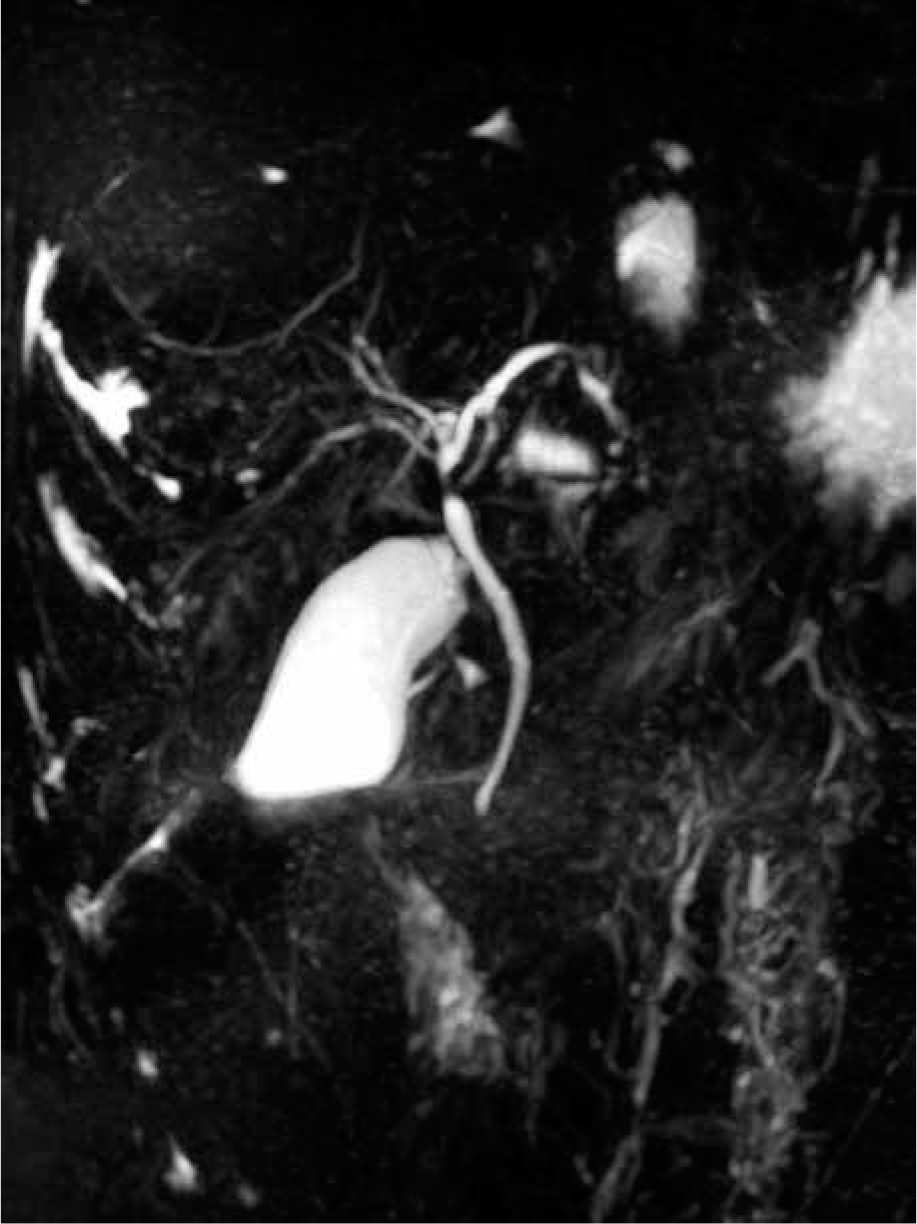

Ambulatory performed laboratory investigation confirmed increases in ALT (1084 U/l) and AST (1543 U/l) activity levels, as a result of which the boy was re-admitted to the hospital. Physical examination showed conjunctival icterus. Laboratory tests revealed increased levels of ALT (605 U/l), AST (1040 U/l), GGT (47 U/l), total bilirubin (2.55 mg/dl) and direct bilirubin (1.99 mg/dl), bile acids (364 µmol/l), as well as serum IgG (17.1 g/l), hypergammaglobulinaemia (23.9%), deranged coagulation profile (activated partial thromboplastin time 35 s, norm: 21.1-32 s, prothrombin time 15.7 s, norm: 10.4-14 s, fibrinogen 94 mg/dl, norm: 200-360 mg/dl, antithrombin 52%, norm: 80-120%) and positive ASMA (1 : 40). Ultrasonography of the abdomen showed only a small volume of pelvic free fluid. Doppler ultrasound of the hepatic vessels showed a dilated portal vein (14 mm) without other abnormalities at the level of the hepatic veins. The patient was further investigated with magnetic resonance cholangiopancreatography (MRCP), which demonstrated heterogeneous liver enhancement with an increased T2 signal predominantly in the left hepatic lobe, multifocal stricturing and dilation of intrahepatic and extrahepatic bile ducts (Fig. 1).